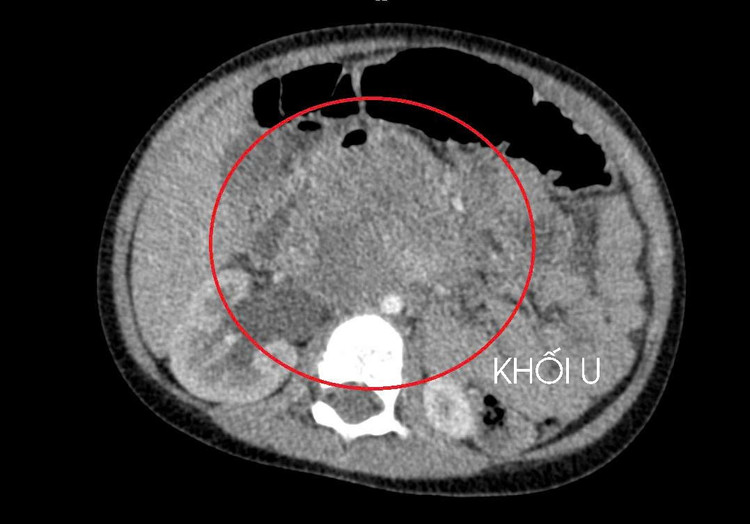

Qua thăm khám lâm sàng, chụp cắt lớp vi tính ổ bụng và siêu âm, các bác sĩ phát hiện một khối u lớn sau phúc mạc, chèn ép thận. Sau quá trình đánh giá toàn diện, kết quả cho thấy bé mắc ung thư tinh hoàn, theo dõi di căn gan và phổi.

Hình ảnh tổn thương di căn - Ảnh BVCC